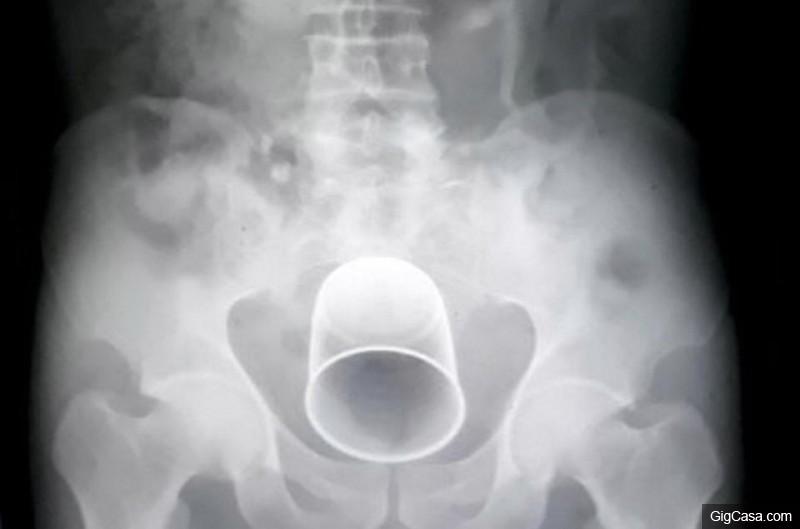

▼原來他的下腹部竟然卡了一個超巨大的杯狀物!

醫生發現這樣的狀況之後也嚇傻了,連忙為他進行手術,最後耗費一個半小時,終於從他體內取出異物。

▼那個異物竟然是個長達21公分的鋼杯!根據狀況推斷,只有可能是那個密醫塞進去的。